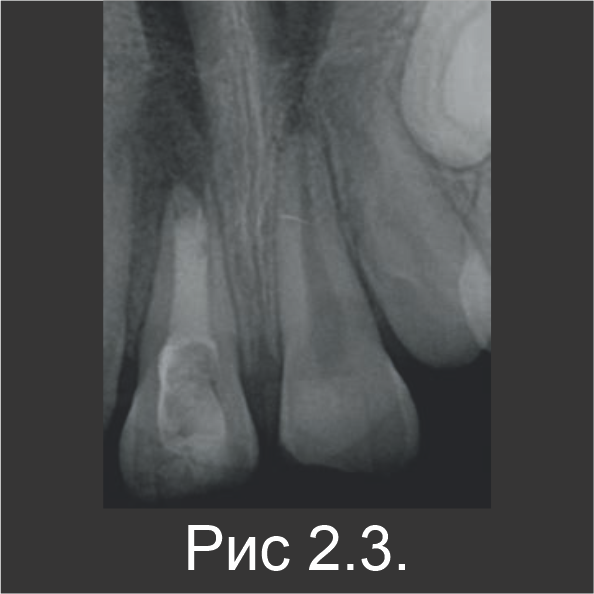

9-летнего мальчика направили на лечение инфицированного корневого канала зуба 11. За 10 месяцев до этого, т.е. в возрасте 8 лет, он перенес травму зубов, в результате которой были вывихнуты зубы 11 и 21, образовались неосложненные переломы в эмалево-дентинном соединении, а также увеличилась подвижность зубов. На оба травмированных зуба наложили шины на 2 недели, затем их восстановили с помощью композита. В ходе клинического обследования со щечной стороны зуба 11 обнаружили свищ (рис. 2.1). По рентгенограмме установили, что оба центральных резца развиваются ассиметрично, а в области апекса зуба 11 есть участок просветления (рис. 2.2).

Резец остался в несформированном состоянии (с открытым апексом), остановившись в развитии по причине некроза пульпы. В течение первого посещения резец вскрыли, после чего корневой канал промыли гипохлоритом натрия, чтобы удалить некротические ткани. Затем канал просушили и заполнили пастообразной гидроокисью кальция на 2 недели (рис. 2.3). В течение второго посещения, после удаления гидроксида кальция канал заполнили Biodentine™ (рис. 2.4).